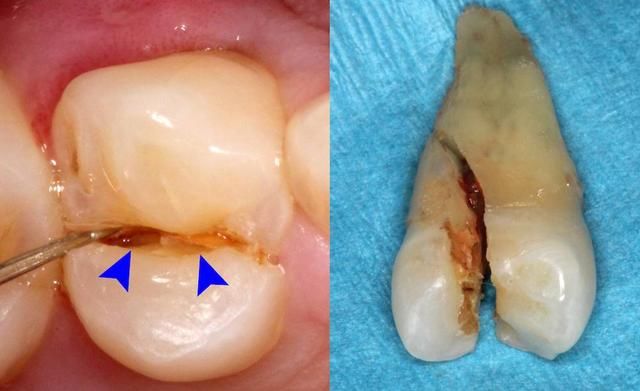

1、不滿足拔牙適應症: 不是所有人都能拔牙的,除非是多生牙、雙排牙以及位置不正的智齒等,醫生是建議拔除的。其他的牙齒情況,無論是齲齒,還是牙周炎、牙根尖周炎或者是牙齒畸形等,需要先拍片確定是否需要拔牙。一般不會(hui) 輕易拔除,會(hui) 嚴(yan) 格堅持拔牙準則:“該拔的拔,不該拔的堅決(jue) 不拔,可拔可不拔的商量著拔。”